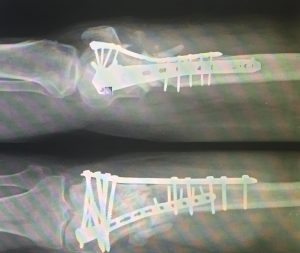

Orthopaedics Home Orthopaedics Orthopedic surgeon studying a x-ray of a broken radius bone in theater after correctional surgery. Man massaging painful wrist on a white background. Pain concept